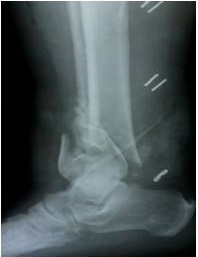

Se trata de un paciente masculino de 49 años de edad, con antecedentes de hipertensión arterial, atendido en el Hospital Gustavo Aldereguía Lima, de Cienfuegos, tras haber sufrido una caída desde una altura, que le produjo una fractura abierta tipo 2 de Gustillo-Anderson (Figura 1) y que se pudiera clasificar además como una fractura A3 según la fractura extrarticular con conminución metafisaria (AO/OTA). (Figuras 2 y 3).

En caso de dudas sobre la extensión de las fracturas, tras la evaluación radiológica se puede indicar una tomografía axial de la zona. En este caso no se consideró necesaria la realización del estudio por tratarse de una fractura extra articular.